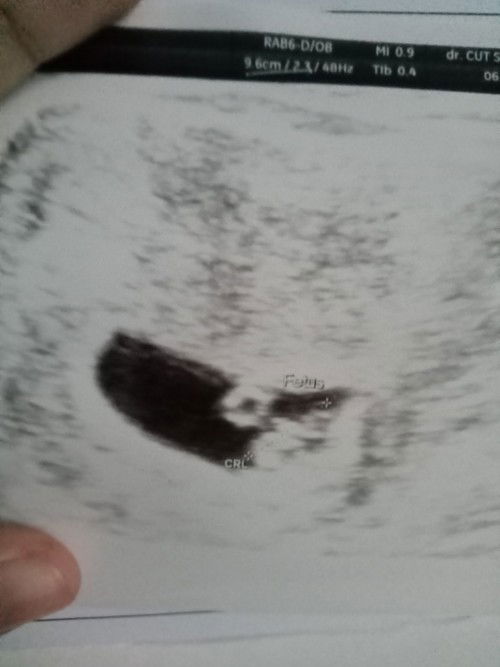

Jadi saya nge flak coklat terus udah 4 harian pas saya USG ke dokter udah ada detang jantung dan janin nya sehat dan berkembang kata dokter kurang minum air disuruh bedres sama dikasih penguat bunda bunda disini ada gak yang udah USG tapi kantung kehamilannya seperti bulan sabit # ##seriusnanya #bantusharing #ingintahu #firstmom